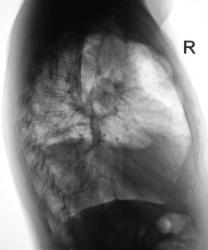

Цирротический туберкулёз верхней доли правого лёгкого со смещением органов средостения. Случай верифицирован (вскрытие).